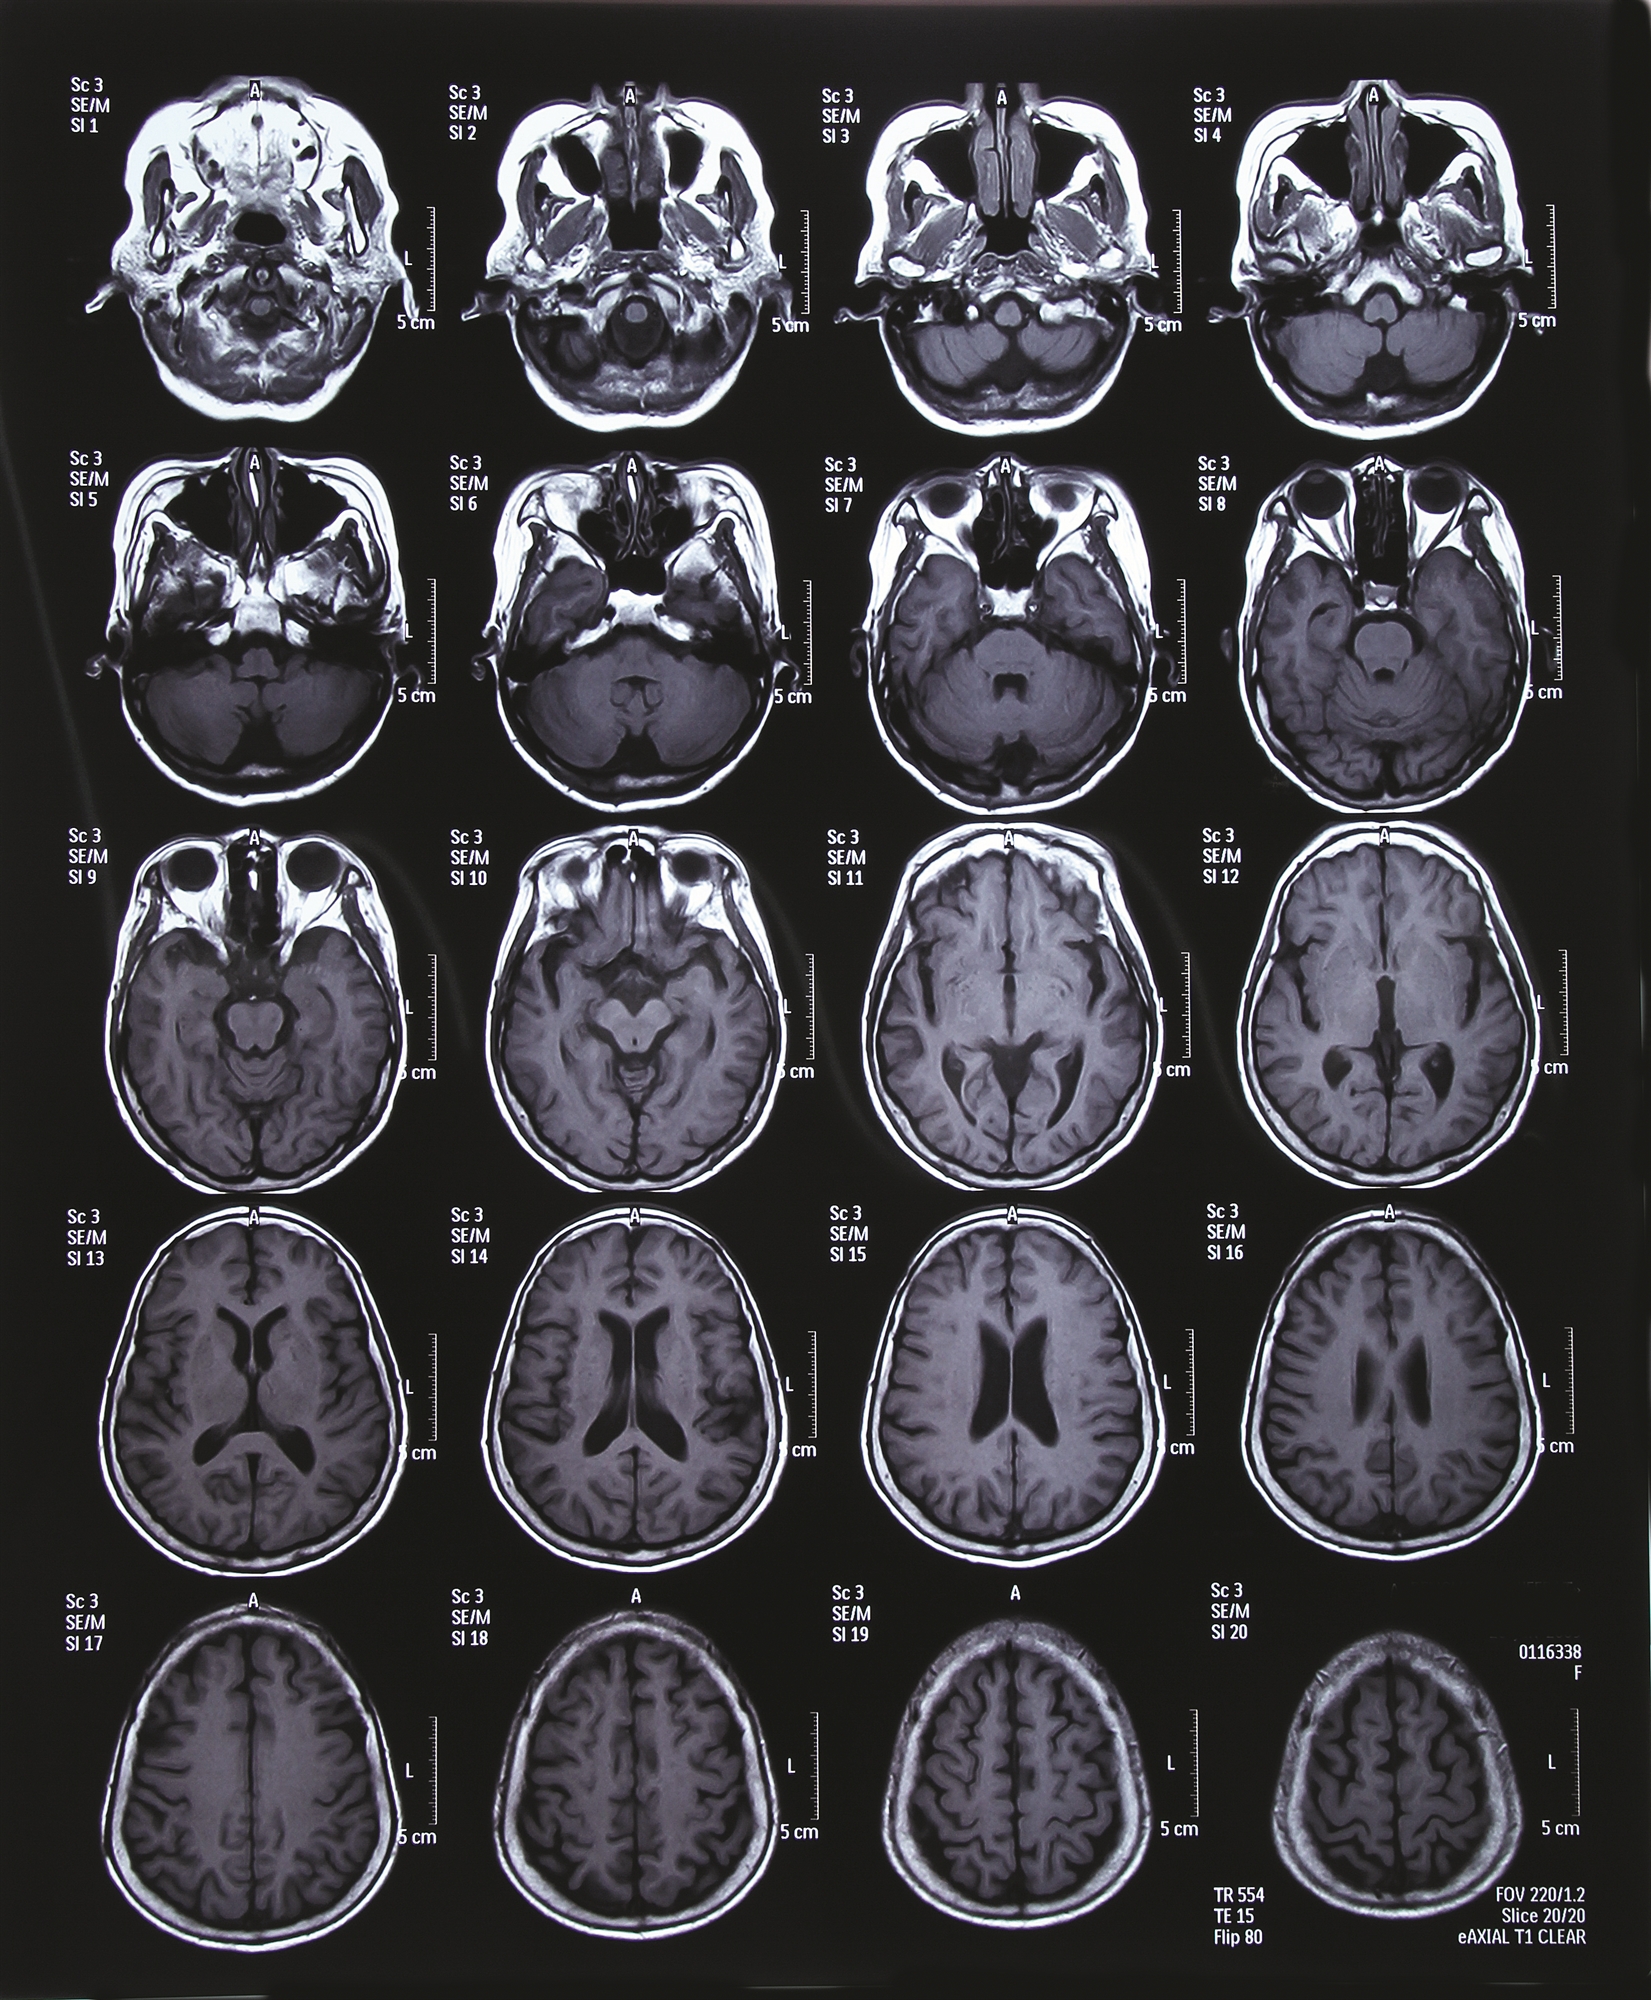

«Ένα μεμονωμένο μικροσκοπικό αγγειακό εγκεφαλικό επεισόδιο δεν είναι ορατό σε μια τομογραφία εγκεφάλου. Όμως, αν συσσωρευτούν δεκάδες ή εκατοντάδες, εμφανίζονται ως πιο φωτεινές περιοχές σε μια μαγνητική τομογραφία (MRI)», δηλώνει ο δρ Andrew Budson, επικεφαλής του Τμήματος Γνωστικής και Συμπεριφορικής Νευρολογίας στο Σύστημα Υγείας Βετεράνων της Βοστώνης και λέκτορας Νευρολογίας στην Ιατρική Σχολή του Χάρβαρντ. Οι φωτεινές κηλίδες είναι γνωστές ως αλλοιώσεις της λευκής ουσίας (η λευκή ουσία αποτελείται από δέσμες νευρικών ινών που συνδέουν τα κύτταρα του εγκεφάλου).

Οι τομογραφίες εγκεφάλου των περισσότερων ηλικιωμένων εμφανίζουν κάποιες ενδείξεις αλλοιώσεων της λευκής ουσίας. Αναγνωρίζονται ως δείκτες των τυπικών γνωστικών αλλαγών που επέρχονται με την ηλικία. Όμως τα άτομα που έχουν υποστεί καρδιακή προσβολή φαίνεται ότι έχουν περισσότερους παράγοντες κινδύνου για μικροσκοπικά αγγειακά εγκεφαλικά επεισόδια (ίσως και κάποιους που δεν έχουν αναγνωριστεί ακόμη). Ως αποτέλεσμα, φαίνεται ότι έχουν περισσότερες αλλοιώσεις της λευκής ουσίας και εμφανίζουν ακόμη μεγαλύτερη έκπτωση της γνωστικής λειτουργίας. «Ως νευρολόγος που εξετάζει τομογραφίες εγκεφάλου συνεχώς, πιστεύω ότι αυτή είναι η πιο πιθανή εξήγηση», δηλώνει ο δρ Budson.